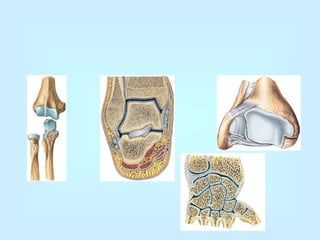

El cuerpo humano tiene diversos tipos de articulaciones móviles.  La cadera  y el  hombro  son articulaciones del tipo  esfera-cavidad , que permiten movimientos libres en todas las direcciones. Los  codos , las  rodillas  y los  dedos  tienen articulaciones en  bisagra , de modo que solo es posible la movilidad en un plano. Las articulaciones  en pivote , que permiten solo la rotación, son características de las dos primeras vértebras; es, además, la articulación que hace posible que gires la cabeza de un lado a otro. Y, por último, las articulaciones  deslizantes , donde las superficies óseas se mueven separadas por distancias muy cortas. Se observan entre diferentes huesos de la muñeca y del tobillo.

Articulaciones Las articulaciones móviles presentan los siguientes elementos:  superficie articular, lisa, generalmente entre dos epífisis de huesos largos;  un cartílago articular, que ocupa el espacio entre un hueso y otro, blanco, liso y brillante, que facilita el deslizamiento de una superficie sobre otra;  Cápsula fibrosa, que se inserta en los extremos de cada uno de los huesos que forman la articulación  La membrana sinovial, que segrega el líquido que lubrica todas las articulaciones,  Ligamentos articulares, cordones de tejido conjuntivo que impiden la separación de los huesos que integran la articulación.

Articulaciones Las articulacionesmóviles presentan los siguientes elementos: superficie articular, lisa, generalmente entre dos epífisis de huesos largos; un cartílago articular, que ocupa el espacio entre un hueso y otro, blanco, liso y brillante, que facilita el deslizamiento de una superficie sobre otra; Cápsula fibrosa, que se inserta en los extremos de cada uno de los huesos que forman la articulación La membrana sinovial, que segrega el líquido que lubrica todas las articulaciones, Ligamentos articulares, cordones de tejido conjuntivo que impiden la separación de los huesos que integran la articulación.

Esqueleto humano Enlas rodillas, codos y dedos son de encaje recíproco. En la rodilla, la de mayor tamaño, el fémur (el hueso más largo del esqueleto) y la tibia forman una articulación de encaje recíproco, reforzada por ligamentos que conectan en forma cruzada ambos huesos y una fuerte cápsula articular. Los extremos femorales, redondeados, se hallan situados por detrás de la rótula. La articulación del hombro está compuesta por una esfera y una cavidad, lo que permite una mayor variedad de movimientos.

La de lacadera, sobre la que descansa el peso del cuerpo, está formada por la cavidad coxal, en la que se inserta la cabeza del fémur. Por otro lado, un tendón que cruza desde el fémur hasta el coxal mantiene la articulación en la posición adecuada. Las articulaciones semimóviles son las que aparecen entre dos vértebras; las dos caras que se unen son ligeramente cóncavas y están revestidas por una fina membrana de tejido cartilaginoso. Los ligamentos interóseos permiten la flexión y expansión de la columna vertebral. Las articulaciones inmóviles se encuentran en la cabeza; como ejemplo puede citarse la que existe entre los huesos parietal y frontal del cráneo, unidos mediante una serie de salientes, a modo de dientes, que coinciden a la perfección.